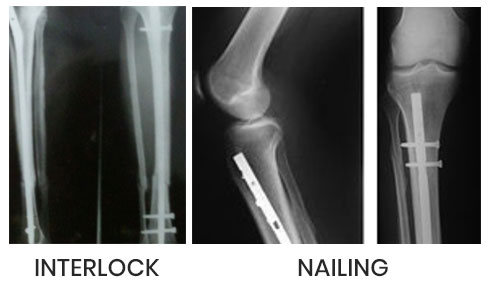

The centre runs 24 hrs emergency for accident cases managed by well equipped & trained staff all around the clock. Dr. Sagar Rane personally looks up all trauma cases & operates himself. All surgeries one done under C-ARM (scan) machine. So perfect results are achieved. He does vascular surgery /repair himself.

Under C-ARM all surgeries done through key hole incision and under bone scan control which gives 100% results.